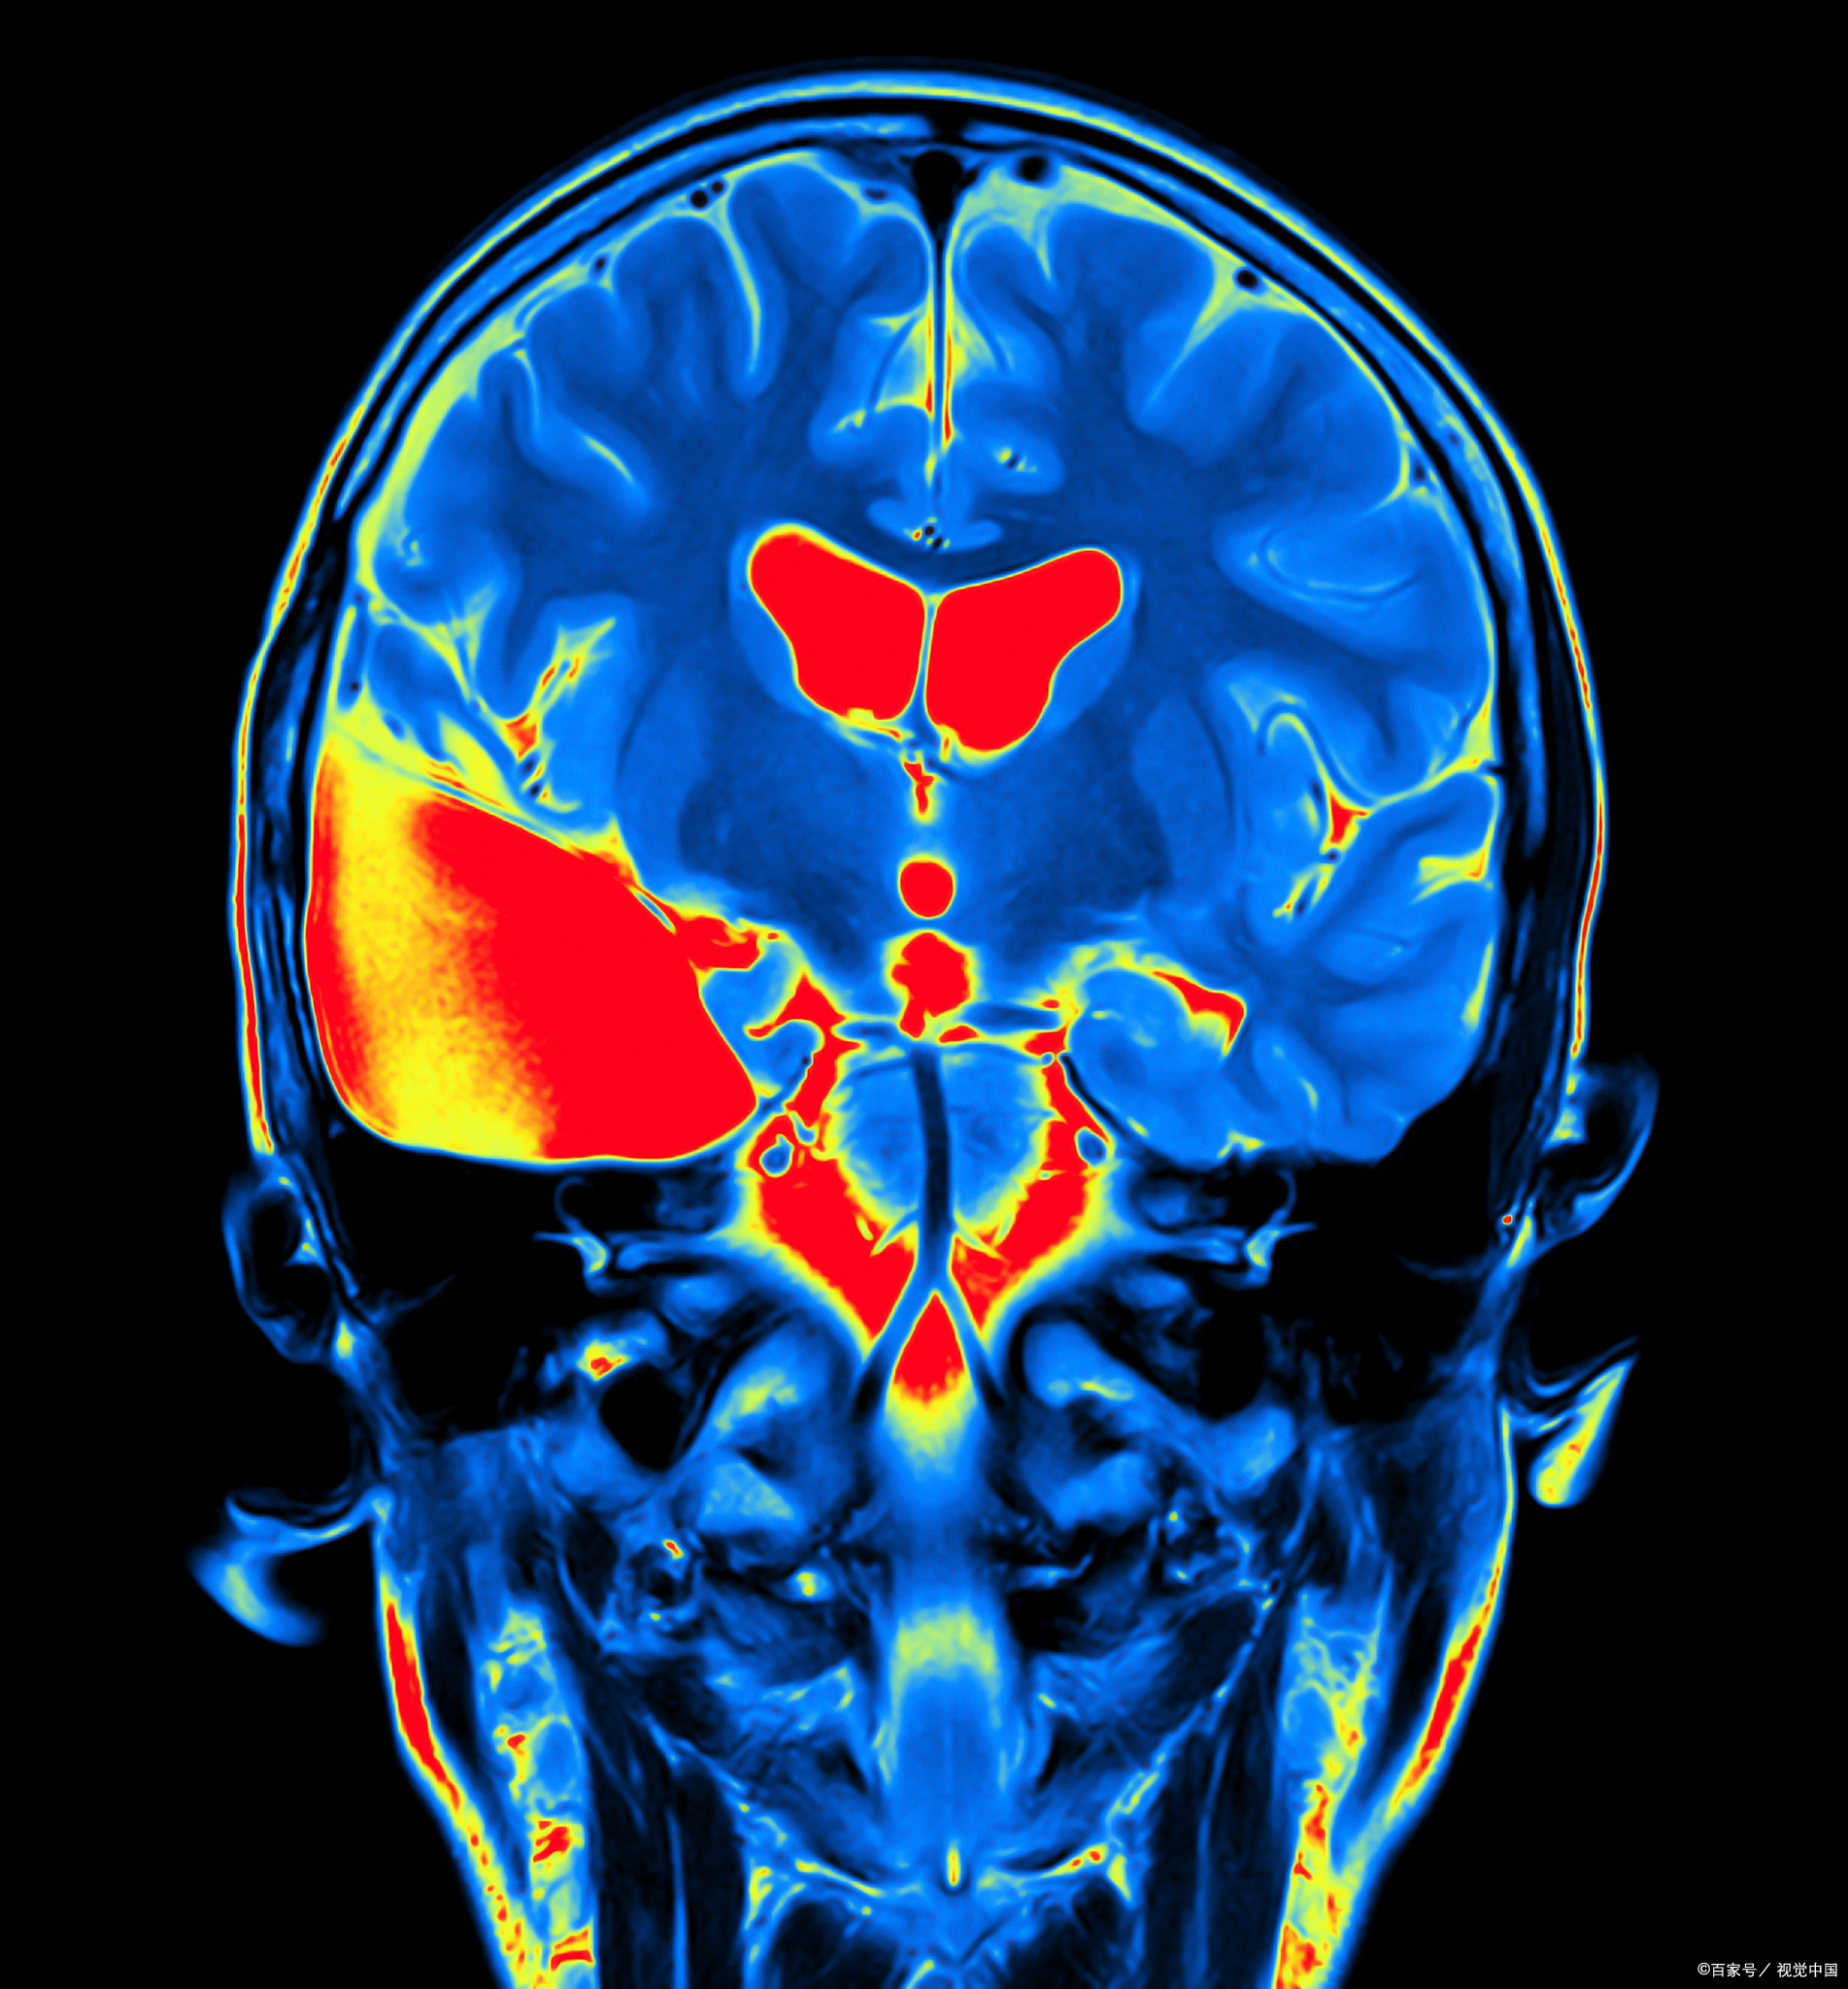

可以通过成像技术观察和记录脑部结构和功能上的变化

世界上最强大的核磁共振成像仪首次捕捉到令人震惊的脑部扫描